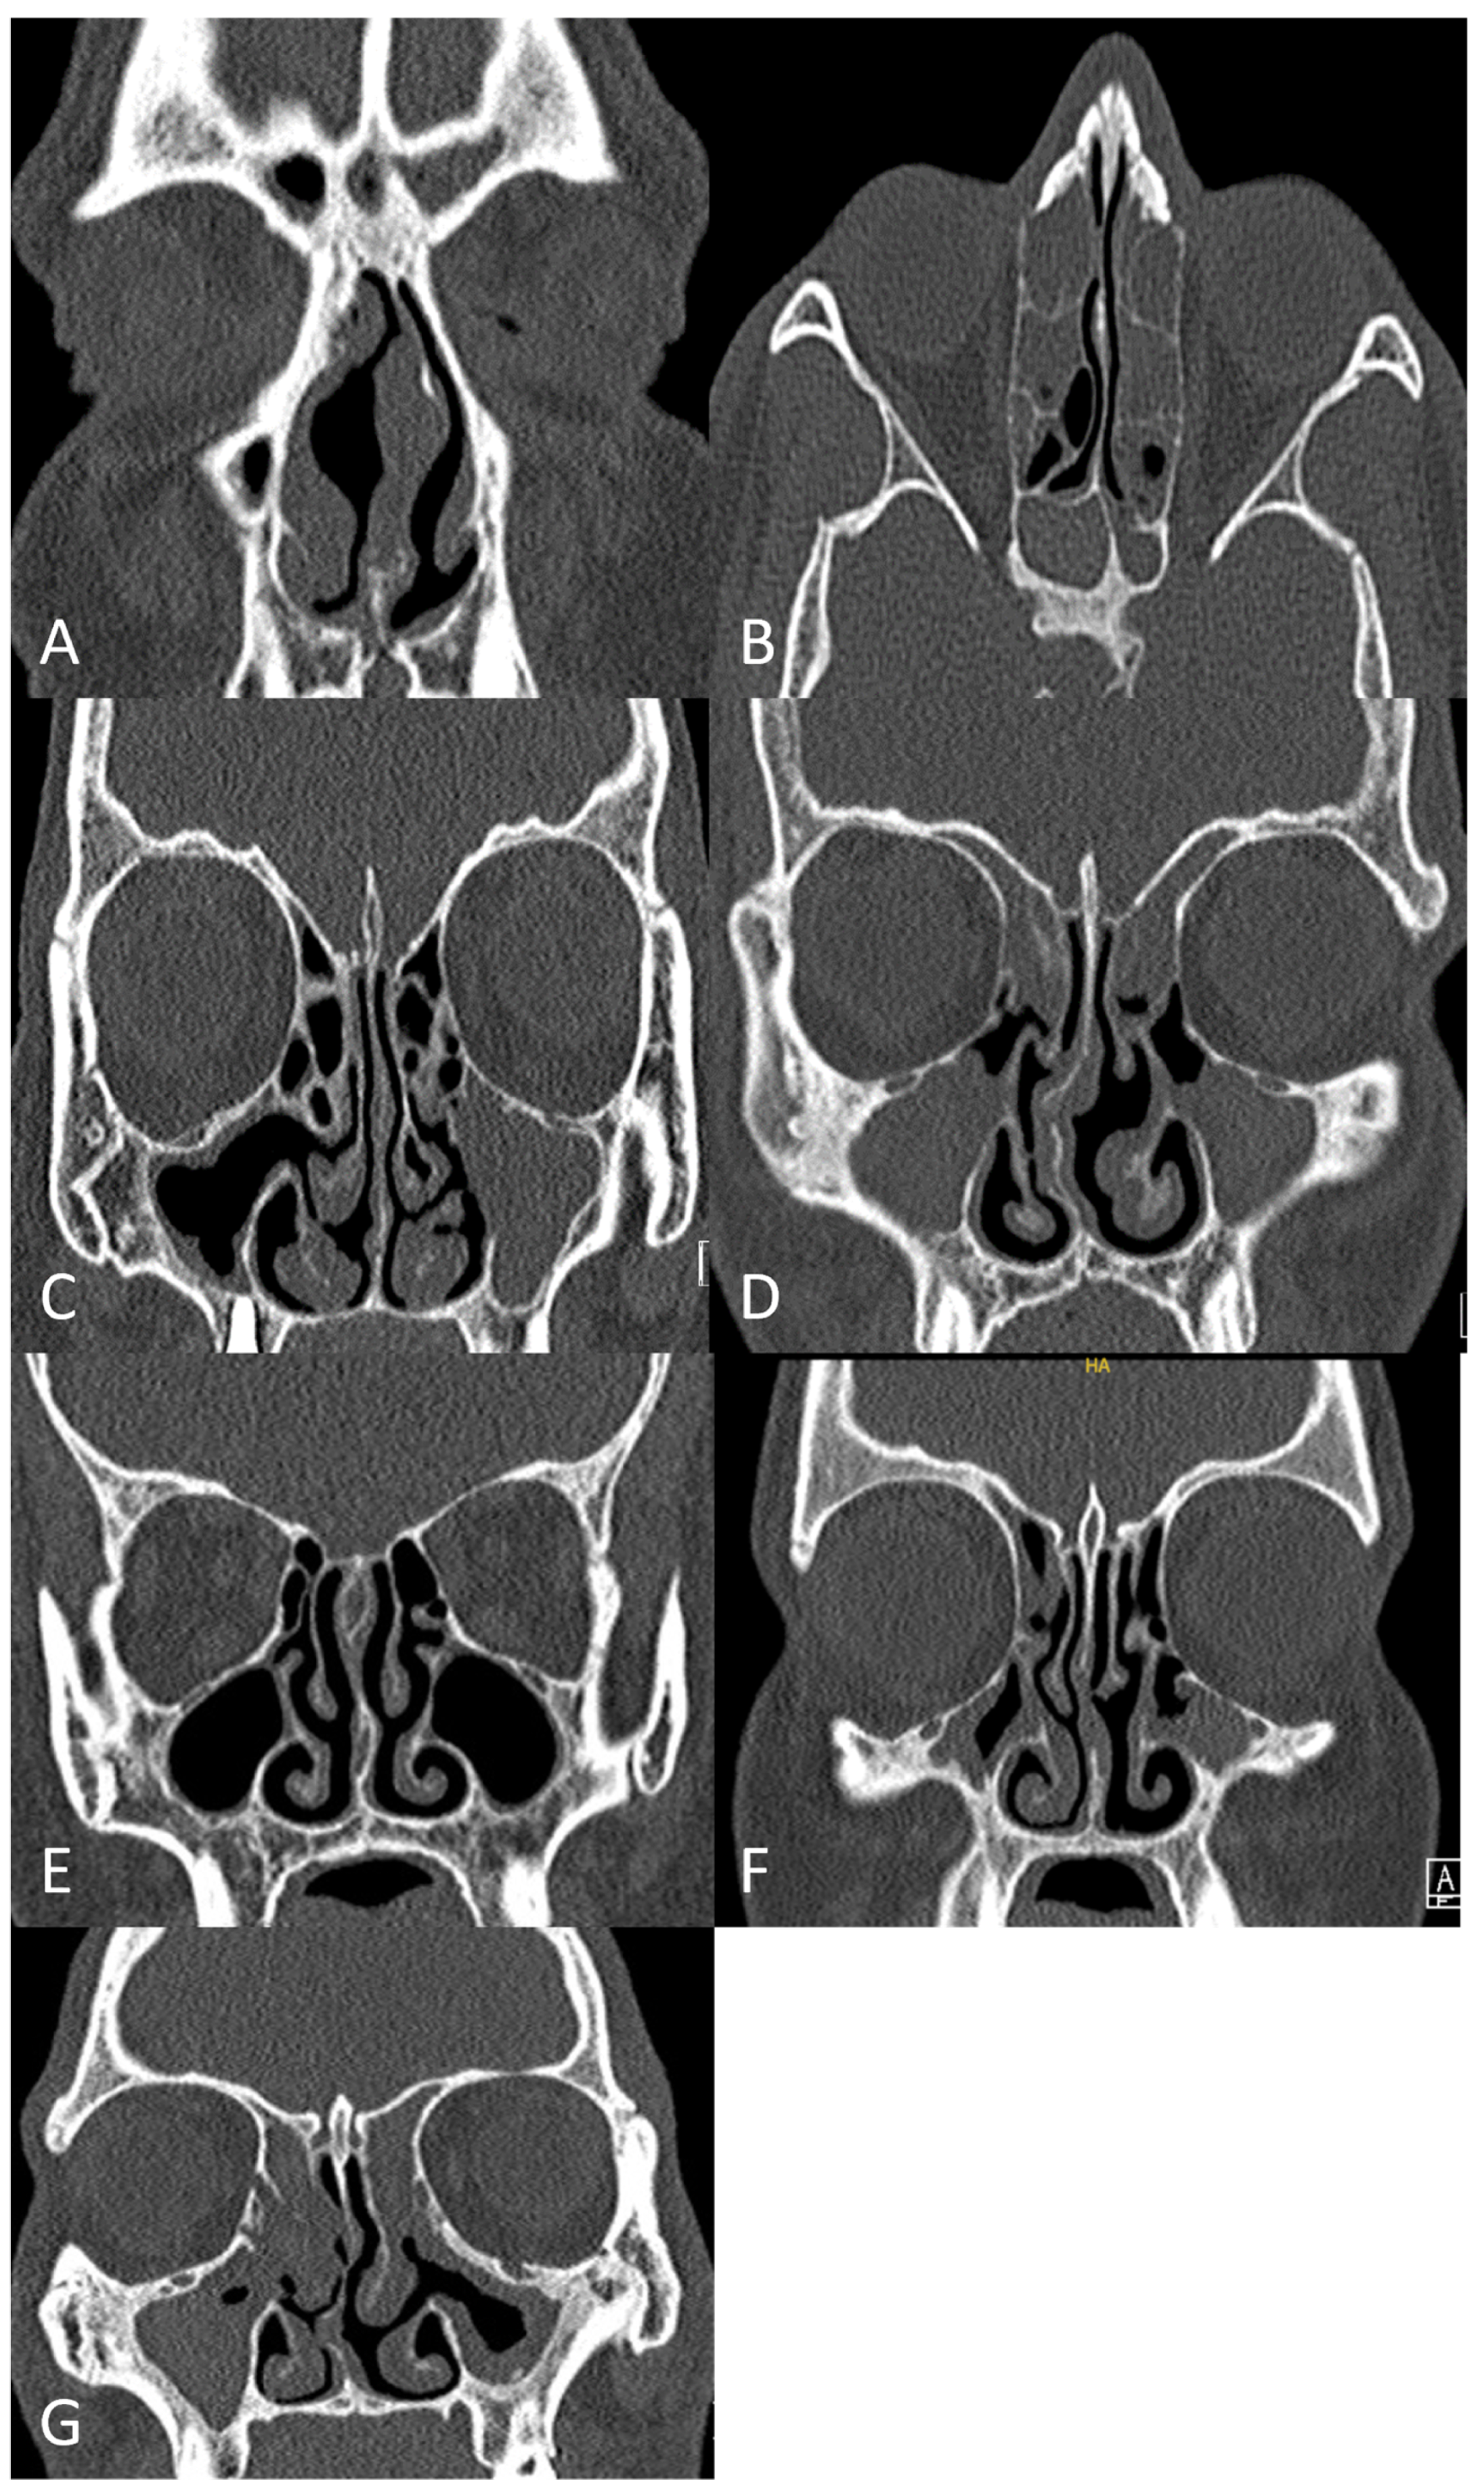

1. Introduction

2.4. Lund–Mackay Score (LMS) and Main Nasal Cavity Score (MNCS)